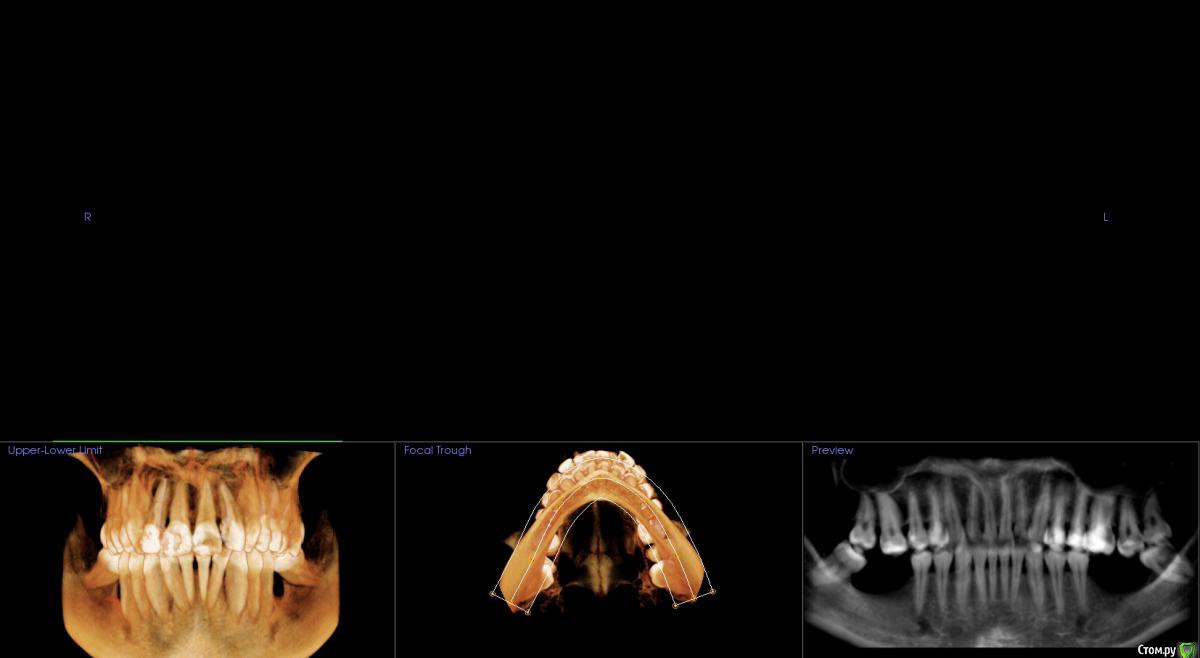

Господа как лучше тут поступить? поменьше бы рисков)

" всеводинэтап"крыша гаража" и латерализация отменяются)))

вижу вариант только с сеткой.

Из того что разобрал по срезам мне кажется можно медиально расщепить и притопить, дистально 4х6 поставить (астра, штрауманн...). Посмотрите, помещаются ли такие импланты. Травма меньше, быстрее и меньше рисков.

Сделайте нкр с медиальными болтами, дистальные глубже установите.

Тогда десну аля шашлычки и фдм отсроченно.

Далее временное протезирование.